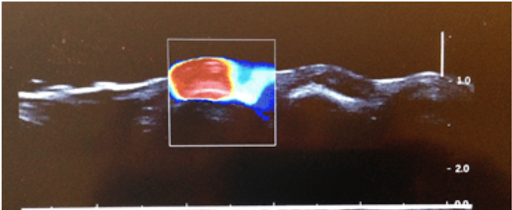

Post-surgical neuroma before DFR…

and 2 days after one 2-hour DFR treatment…

High Frequency Shear Wave Elastography/HFSWE is non-invasive ultrasound imaging technique that makes the presence and absence of otherwise invisible adhesions visible and quantifiable. On the left, the red mass is the adhesion. On the right, you can see that following DFR Therapy, the adhesion is broken up, the scar tissue has been pulled apart and circulation has returned to the tissue.